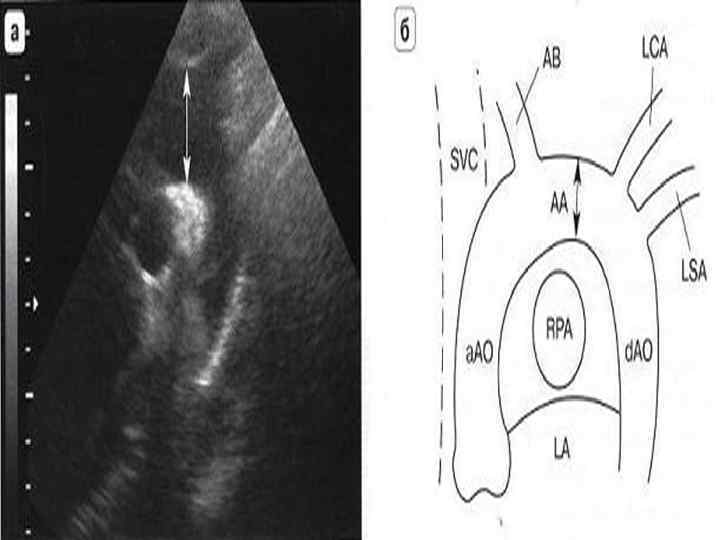

Ультразвуковая анатомия сердца В эхокардиографии используют ряд доступов к сердцу и магистральным сосудам: • Левый парастернальный • Апикальный • Субкостальный • Супрастернальный • Правый парастернальный